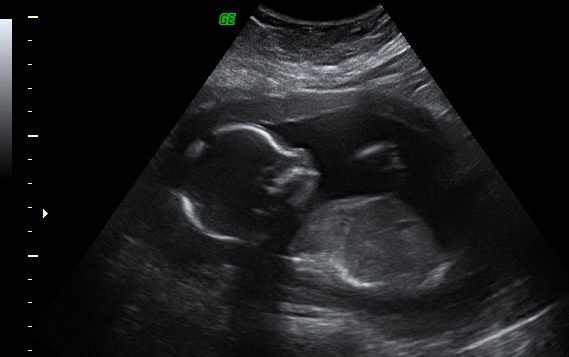

Sixth pregnancy journey-2

結果說好要寫第六次懷孕的續集,一拖就是將近半年後。

雖然已經離懷孕好久了,但還是要把紀錄寫好。在美國確定心跳後,

雖然不和台灣一樣會發一本媽媽手冊,但是相同的,有看到心跳後才是正式的確認懷孕的旅程 ~